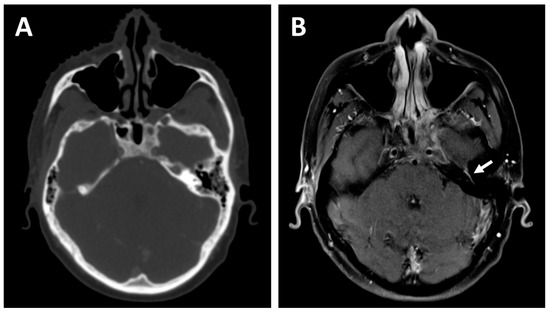

2.2. Lymph Node Evaluation